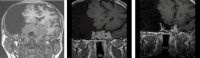

Methods: Thirty-three patients with giant prolactinomas (≥ 4 cm) were treated with primary pharmacotherapy. We assessed pituitary function, the effect of therapy and different dosing regimens on prolactin normalisation and tumour size, the effect of surgery for complications and the effect of radiotherapy in resistant patients.

Results: Out of thirty-three consecutive patients (mean age 42 years), 27 were men, and 6 were women. The baseline mean prolactin concentration was 7506 µg/L. The treatment of choice was cabergoline in 30 patients, terguride in 2 patients, and bromocriptine in 1 patient. In patients receiving a high dose of cabergoline (3.5 mg weekly), we observed a faster normalisation of prolactin but not faster reduction in tumour size than in patients receiving a low dose (1-2.5 mg weekly). A total of 9/33 (27 %) patients underwent surgery for complications, 3 of whom were irradiated by Leksell gamma knife for partial resistance. In 4/33 patients we were able to stop pharmacotherapy after 10-20 years of treatment. The remaining 29/33 patients remained on pharmacological treatment.